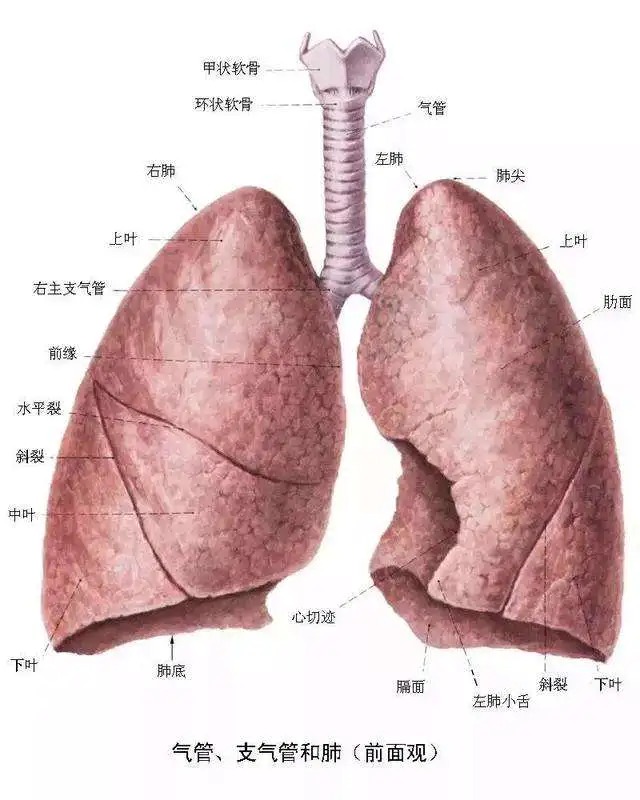

(二)颜色肺位于胸腔内,纵隔两侧,因心位置偏左,故左肺狭长,右肺略宽短

第四节 肺尖 肺 肺尖 肺底(膈面) 肺的外形 前缘 下缘 肋面 内侧面

好漂亮的肺部解剖!

肺部的解剖结构1

肺段分解 - 美篇